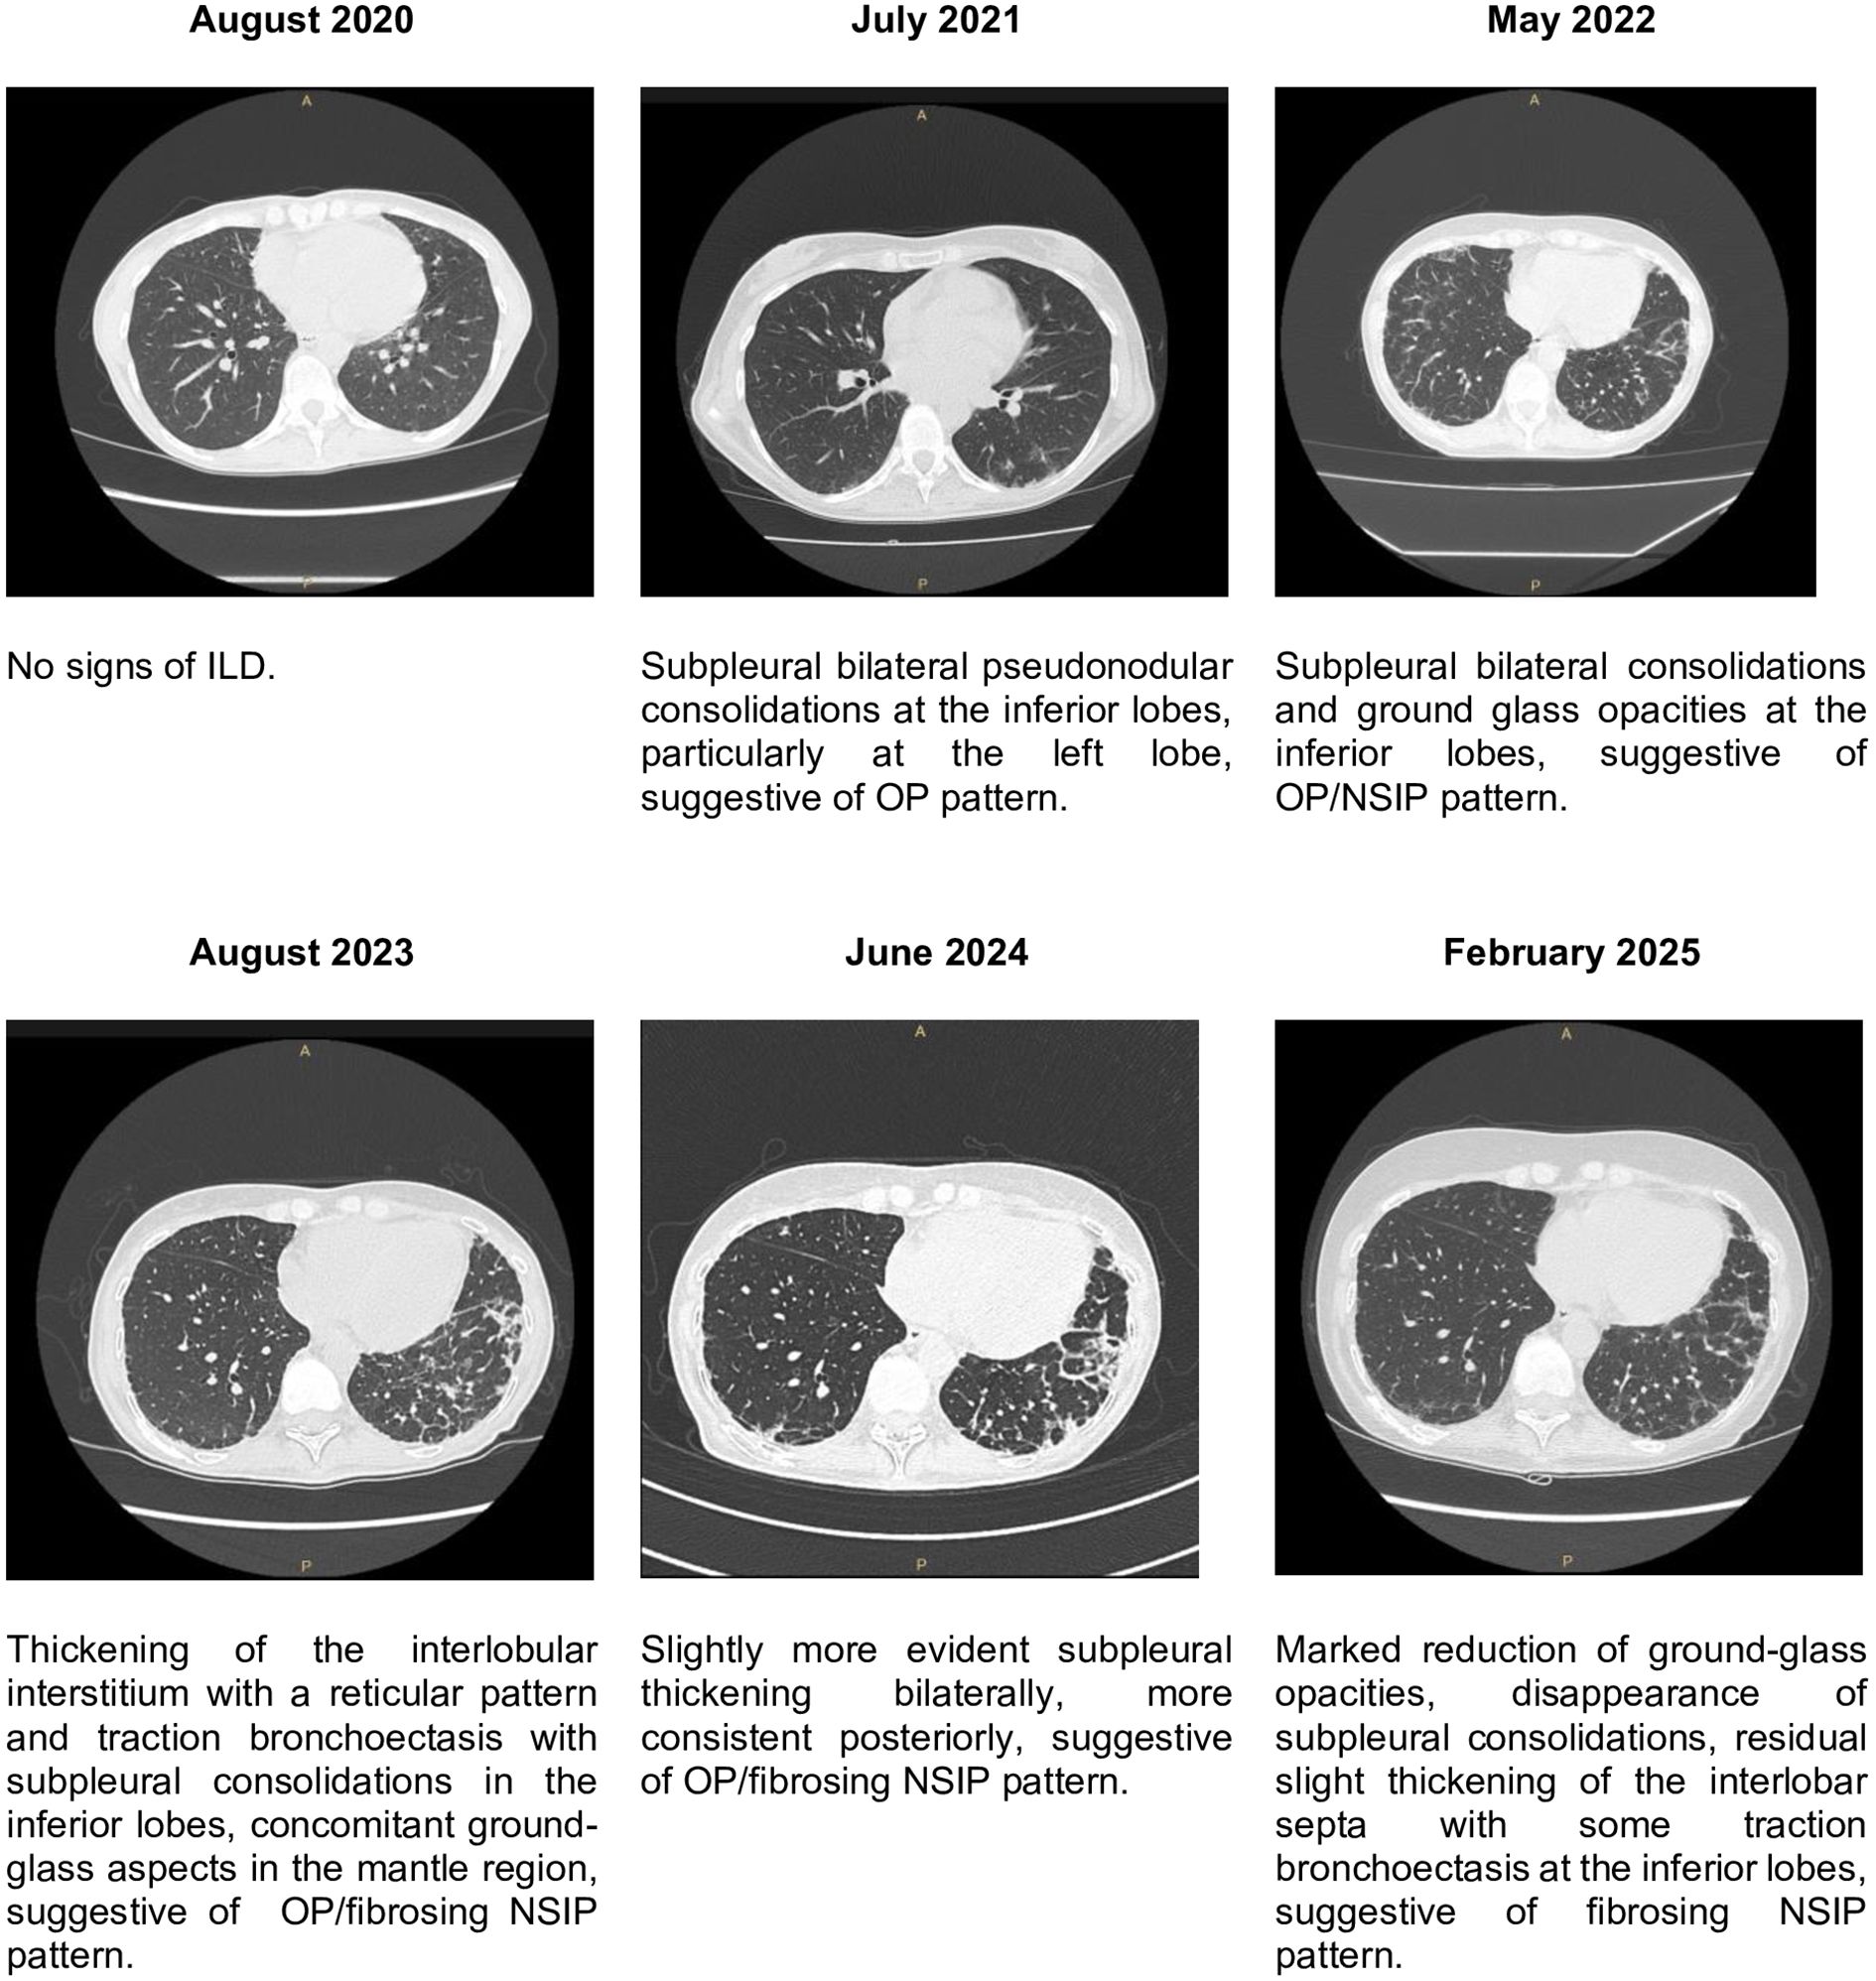

A 55-year-old woman was diagnosed with anti-melanoma differentiation-associated gene 5 (anti-MDA5) positive dermatomyositis (DM) in 2020, having low grade fever, weight loss, arthritis in small joint of hands, erythematous-desquamative lesions on hands, cuticle dystrophy and severe skin ulcerations. Firstly, she was treated with cyclosporine (CsA), soon discontinued due to gastrointestinal intolerance. She was subsequently treated with steroid pulses, hydroxychloroquine (HCQ) and mycophenolate (MMF), without improvement. In March 2021 she started therapy with intravenous immunoglobulins (IVIG) and prostanoids, leading to ulcer improvement, but stopped due to gastrointestinal intolerance. A chest high resolution computed tomography (HRCT) done in June 2021 showed interstitial lung disease (ILD). In September 2021 rituximab (RTX) was stopped at the first infusion due to gastrointestinal intolerance. From January 2022 the patient also started to walk with difficulty due to development of deep asthenia. Therapy with various Jak inhibitors was started (first tofacitinib, then baricitinib, finally upadacitinib), leading to improvement of cutaneous ulcers, but stopped every time after a few months due to gastrointestinal intolerance and dizziness. In August 2023 during hospitalization a spirometry showed reduction of diffusion capacity of the lung for the carbon monoxide (DLCO). In June 2024, in consideration of poor disease control and refractoriness of the disease (loss of appetite and weight, worsening of asthenia which forced the patient into a wheelchair, persistence of polyarthritis, skin ulcers, alopecia, Gottron's signs, radiological progression of ILD), she was hospitalized again and Anifrolumab (ANI) was started in July 2024 (300 mg IV every four weeks). After four infusions the patient reported improved appetite with significant weight gain, resolution of arthritis and disappearance of cutaneous ulcers, Gottron's sign and alopecia. In February 2025, after seven ANI infusions, a HRCT demonstrated a significant radiological improvement of the ILD compared to 2024, and spirometry showed significant improvement of DLCO compared to 2023. In this period, no adverse effects were observed from the new therapy. After twelve total infusions, constitutional, articular and cutaneous involvement remained in good control. This case suggests the potential efficacy of ANI in refractory anti-MDA5-positive DM not only on skin manifestation, but also on articular and lung involvement.